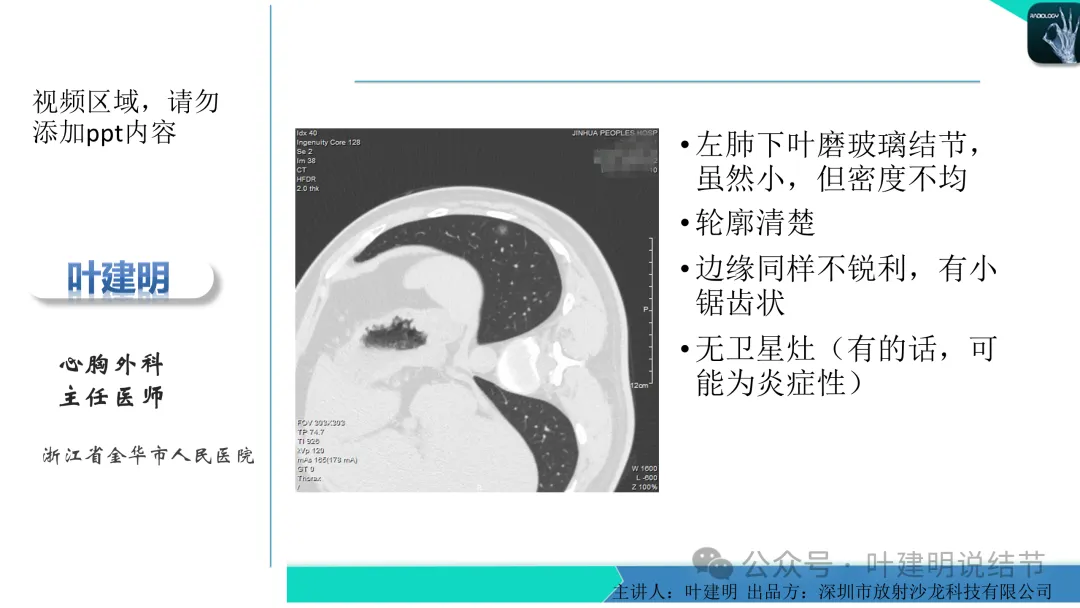

早在2020年时,我受邀在《放射沙龙》做过一个系列的精品课,当时专门总结分析过各类良恶性肺结节与肿块的影像特征,这是当时关于微浸润性腺癌影像特征的分析,今天看来仍基本不太需要改变,大家有兴趣的可以参考: